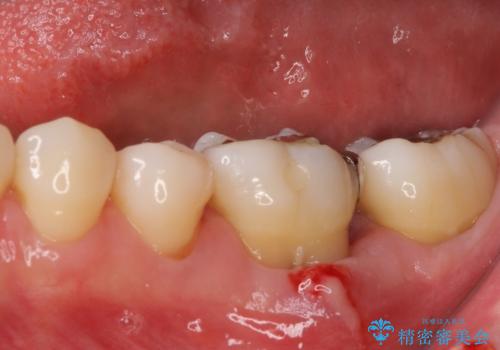

- 以前処置をした歯の歯肉からの出血するとのことで来院された患者様です。

以前むし歯治療をした後から定期的に痛むことがあるとのことで、レントゲン写真より神経組織が失活していることが予想されました。

銀歯を外すと神経組織の一部が取り除かれており、歯根に付け根に穴が空けられている状態でした。

出血の原因は以前の治療で空けられた穴であると考え、封鎖をするとともに根管治療を行い、その後オールセラミッククラウンにて補綴治療を行うこととしました。